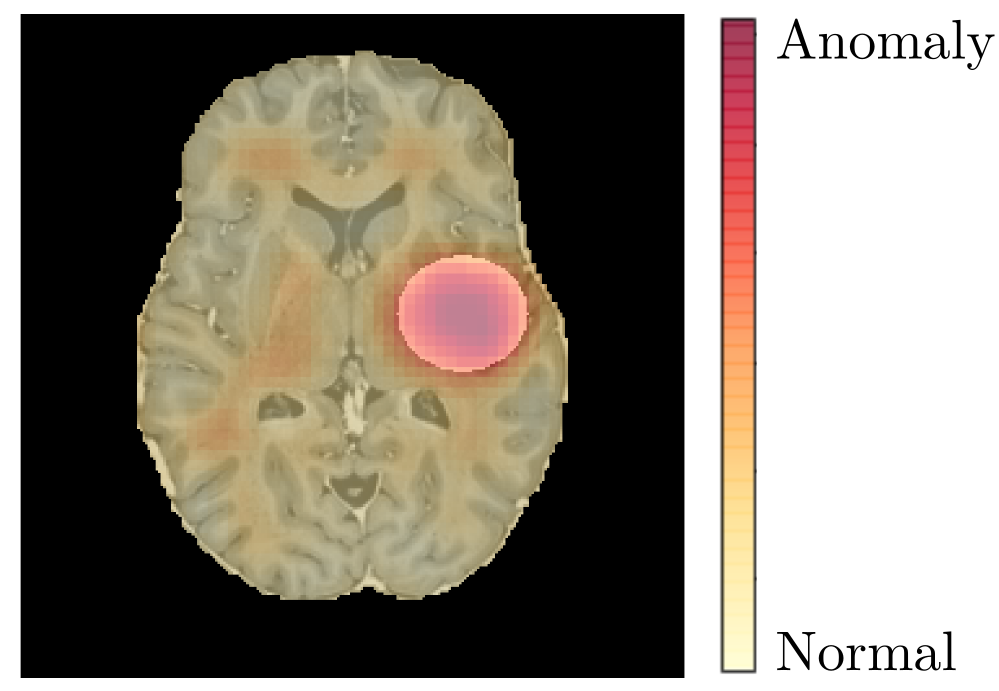

Refer to caption

Figure 5: An example of the result computed by progressive GANomaly with patch size 16x16 of a toy image used for the intensity test. A disk with intensity 1 and diameter 35 mm is inserted in the brain image. This image shows the original input image with a heat map representing the given anomaly scores.